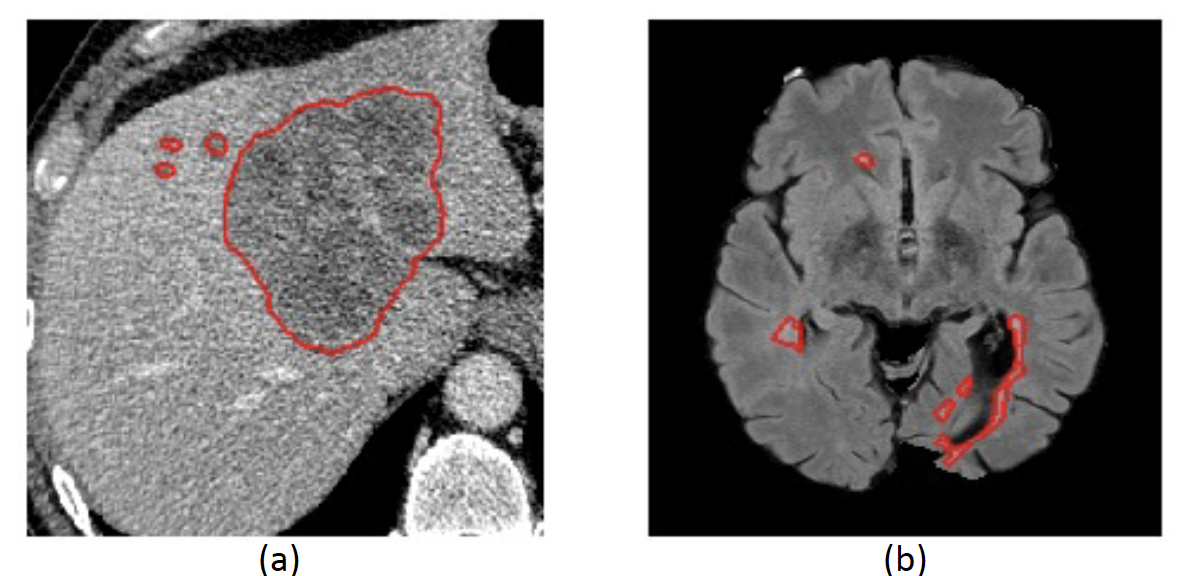

In our experiments, we focus on biomedical imaging applications and demonstrate the effectiveness of our method for segmentation and image reconstruction. We choose these tasks because they can benefit from an increased receptive field, yet are prone to overfitting due to limited training examples. For image segmentation, we consider two problems: liver lesion segmentation [4] and Multiple Sclerosis (MS) lesion segmentation [6] (see Figure 2). For reconstruction, we use T1-weighted axial brain MRI images from the ABIDE dataset [12].

Contrary to what we observed in liver lesion segmentation, the flat Hyper-CNN yields better results than the MB-UNet baseline and the non-local UNet, which have larger receptive fields. This difference is likely because MS lesions are relatively small and more local compared to liver lesions, and thus a larger receptive field is less beneficial for getting an accurate lesion segmentation (Figure 2).